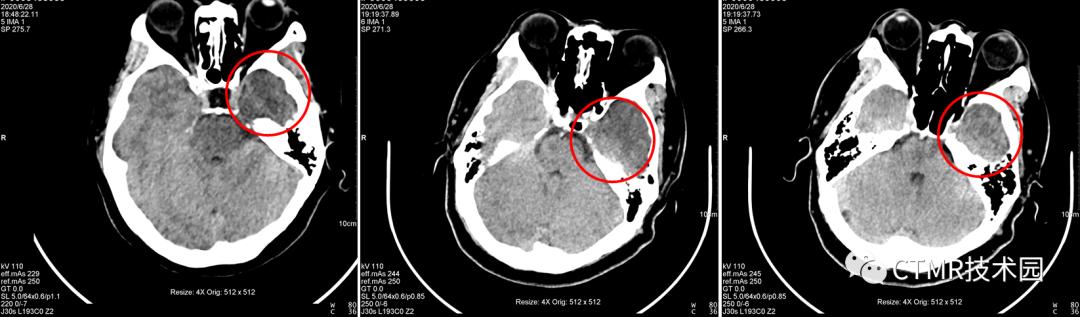

上周我在此机器值班,因为此伪影一直在我脑子里存留,平时在上 Philips Brilliance 64 CT 时,注意观察了下它扫描颅脑的螺距,非常小,可供选择的范围很小,最大可选 0.399。飞利浦的机器比较好的一点就是,它固化了 Scan type,不同的扫描部位/检查方法定义不同的 Scan type,那么在 Brain 扫描类型下,再进一步限制 Collimitation,螺距,Rotation time 等一系列参数,以期获得最佳的的图像质量。那么我就在此机器上尝试选用小螺旋扫描,最小可以改到 0.35,扫了几个病人,伪影完全消失!可以证明,在西门子这台机器上采用大螺距扫描是不合理的,应当也使用小螺距扫描。而且采用小螺距 DLP 还降低了,那么可以进一步增大 QRM,以期获得更好的图像。

而且选用 0.35螺距 eMode 是绿色;如果用 1.1 螺距,那么 eMode 是黄色;如果应用 Adjust,eMode 也变成绿色,且此时当前病人配给的螺距为 0.9,那么它好吗?其实扫描出来的图像大多还是有伪影(从本文开头贴的图片中,有好几个都是 Adjust 后匹配螺距扫描出来的伪影图像)。

探测器宽度约为 4cm,那么在扫描颞部这一区域时,由于螺距 = 1.1>1,或 = 0.9≈1,X 线光子经过对侧的颞区骨头衰减后到达右侧变硬,而且所使用的 kV 是 110kV,不是很高的千伏。又由于颅底这个区域骨质复杂多样,“四面环骨”,那么在右侧的这部分脑组织吸收的 X 线就减少,从而就表现为“暗区”。

问题1:为什么都是经常出现在右侧呢?因为颅脑大致头足范围都差不多,且都是从头向足螺旋扫描,那么螺旋扫描时可能恰好采集伪影区域层块时,是从头左侧先转的一整圈,那么就导致了右侧不在一个完整的环上,因为转过来时已经跑到下一层块了。其实有时病人以 1.1 螺距扫描是没有伪影的,比如头颅扫描范围有所偏差时,那么上一圈扫描结束位置恰好在前 A 位置,那么伪影这一层块扫描时时恰好左侧与右侧颞部基本都在一整圈范围内。这样的情况也是会出现的,那么此时图像上右侧就不会出现明显的暗区伪影。为了验证如此,我还将扫描顺序更改了下,按足向头扫描(如下图),恰恰暗区伪影经常出现在左侧。当然球管到底是怎么转的,如果能够打开机架外壳,仔细看看就好了。